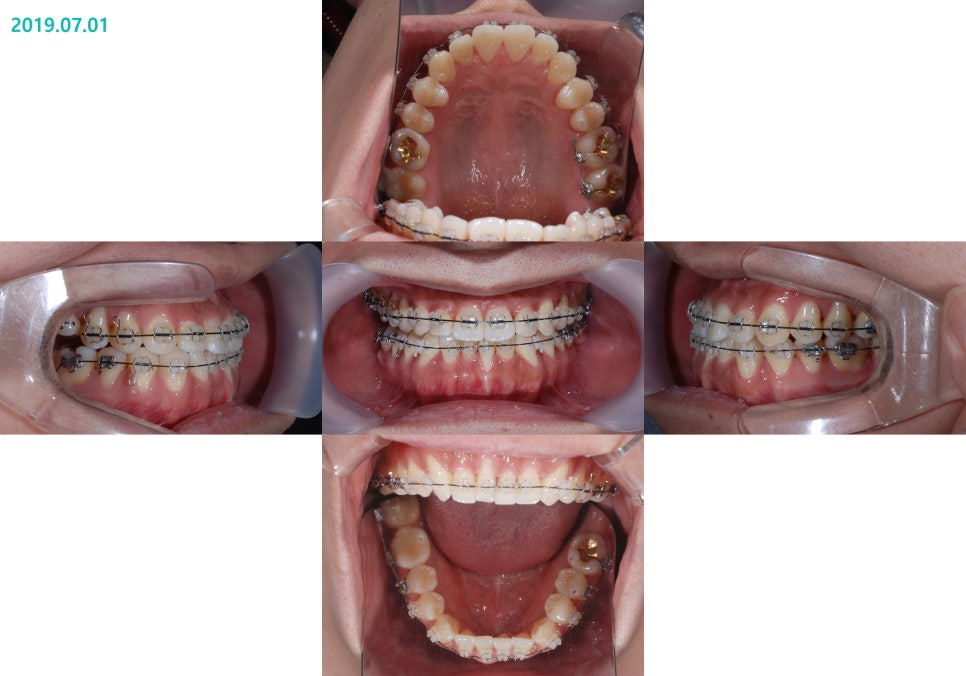

½ÉÇÑ ¹Ý´ë±³ÇÕÀÌ

¾Õ´Ï³¢¸® ¸Â´ê´Â Á¤µµ±îÁö

°³¼±µÈ °ÍÀ» º¼ ¼ö ÀÖ½À´Ï´Ù.

½ÉÇÑ ÁÖ°ÆÅÎÀÌ °³¼±µÇ¸é¼­

À§¾Æ·¡ ¾Õ´Ï°¡

Á¤»óÀûÀ¸·Î ±³ÇÕµÇ°Ô ¹Ù²ï °ÍÀ»

º¼ ¼ö ÀÖ½À´Ï´Ù¸¸

¾ÆÁ÷Àº ±³ÇÕÀÌ ºÒ¾ÈÀüÇÑ »óÅÂÀÔ´Ï´Ù.

±³ÇÕÀ» Á¡Á¡ ´õ ¾ÈÁ¤½Ã۰í

±³ÇÕÀÌ ¾ÈÁ¤µÇ¸é¼­

Ä¡·á¸¦ ¹Þ´Â ȯÀںеµ

°¡¸¸È÷ ÀÖÀ» ¶§

ÀÔ¼úÀ» Àß ´Ù¹°°í, ÄڷΠȣÈíÇϰí

Çô´Â ÀÔõÀå¿¡ Àß ºÙÀ̰í ÀÖ´Â

ÁÁÀº

±¸°­±Ù±â´ÉÀÌ Çü¼ºµÈ °ÍÀ»

È®ÀÎÇÒ ¼ö ÀÖ¾ú½À´Ï´Ù.

µåµð¾î ¸ðµç ±³Á¤Ä¡·á°¡ ³¡³ª°í

½ÉÇÑ ÁÖ°ÆÅÎ ¹× ½ÉÇÑ ºñ´ëĪÀÌ °³¼±µÈ °ÍÀ»

º¼ ¼ö ÀÖ½À´Ï´Ù.

ºñ¼ö¼ú ºñ´ëĪ Ä¡¾Æ ±³Á¤ ÀüÈÄÀÇ »çÁøÀÔ´Ï´Ù.

½ÉÇÑ ¹Ý´ë±³ÇÕÀÌ Àß °³¼±µÈ °ÍÀ»